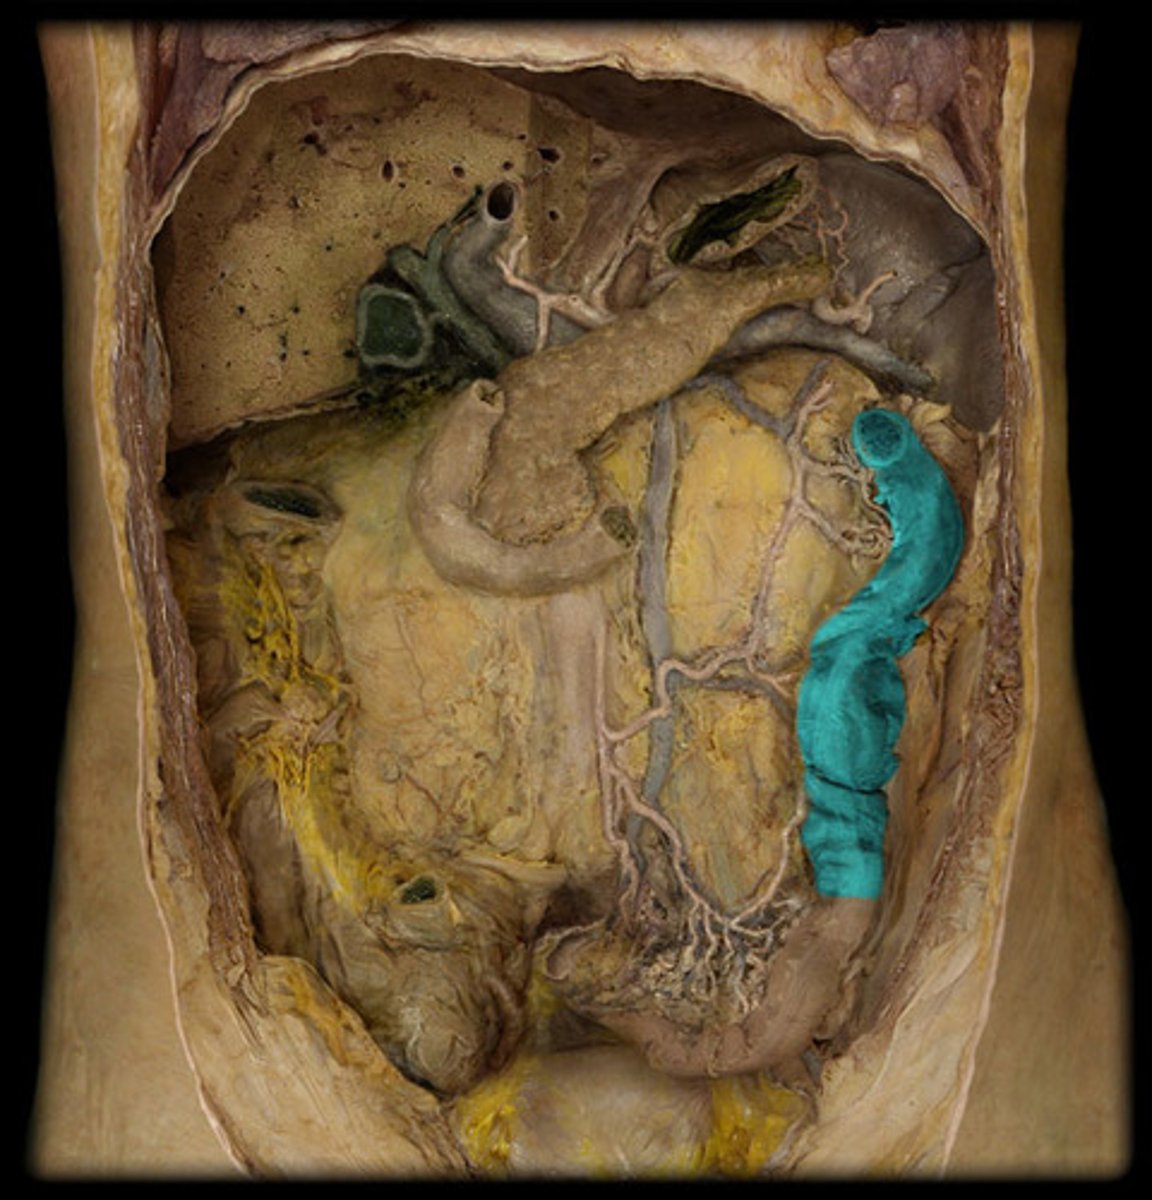

What is this?

Transverse colon

Descending colon

Sigmoid colon